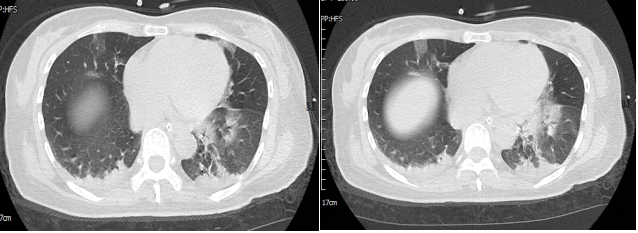

胸部CT:双肺多发斑片状磨玻璃影,双肺下叶胸膜下片状实变影(图2),考虑炎性病变,病毒性肺炎不除外。

图2  患者胸部CT

患者入院肺CT提示:双肺多发斑片状磨玻璃影,双肺下叶胸膜下片状实变影,患者新冠病毒核酸阳性,有乏力、咳嗽、咳痰、发热症状,考虑病毒感染所致肺间质改变,结合患者上述现病史、体征、查体和实验室检查结果,首先考虑患者意识改变为糖尿病性高渗性昏迷可能大,感染为诱发因素,患者病情进展恶化快伴呼吸衰竭,给予报病危、气管插管呼吸机辅助通气、哌拉西林钠他唑巴坦钠4.5g q8h抗感染、奥美拉唑40 mg/d,抑酸护胃预防应激性溃疡、胰岛素泵入降血糖、适当补液、半张氯化钠补液、鼻饲补钾、鼻饲温开水和糖水纠正高钠高氯、肠内营养支持治疗,辅以平喘、化痰、纠正低蛋白、祛痰等对症治疗。

该患者中年女性,既往糖尿病、脑出血术后病史,平素未规律监测血糖,此次急性起病,以呼吸道症状发病,表现为乏力、咳嗽、咳痰、发热不适。查体:双肺呼吸音粗,可闻及湿啰音。胸部CT:双肺多发斑片状磨玻璃影,双肺下叶胸膜下片状实变影,疾病进展迅速,出现意识改变和急性呼吸衰竭,入院诊断考虑重症肺炎,间质性肺改变,该患者既往无肺部基础疾病,多种病因包括感染、结缔组织病、肿瘤或药物肺损伤等,均可引起急性肺损伤,表现为肺间质炎症、纤维化或弥漫性肺损伤改变。

COVID-19主要表现为发热、干咳、咽痛、乏力,以及不典型的上呼吸道症状如肌痛、腹泻、结膜炎、嗅觉味觉减退等,重症患者多在1周内出现呼吸困难和低氧血症,严重者出现急性呼吸窘迫综合征(ARDS)/多器官功能障碍综合征(MODS)。胸部影像学以磨玻璃影或实变为主要表现,可有网格和索条影,但相对较轻,蜂窝或牵张性支气管扩张等肺结构破坏征象不明显,该患者胸部影像学以双肺弥漫性渗出改变为主要表现,临床上急性起病,伴有发热、乏力、咳嗽、咳痰,符合COVID-19临床表现,且患者核酸阳性,入院后完善血培养、痰培养、真菌培养、呼吸道病原学等检查均为阴性,患者既往无心肺基础疾病,无口服特殊药物病史,且此次起病急剧,故考虑COVID-19所致间质肺改变。